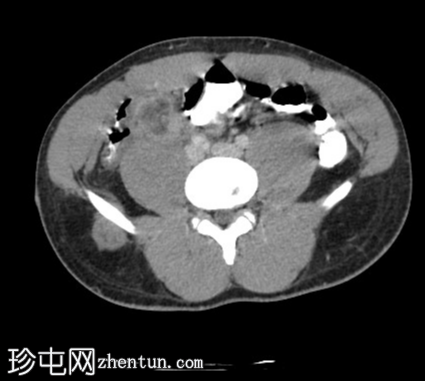

2.jpg

轴位增强扫描

动脉期

阑尾壁增厚并强化。

阑尾与一个厚壁强化脓肿相连,脓肿大小约3.2 x 4.3 cm(横径 x 纵径),内含气体。

周围肠系膜淋巴结肿大,脂肪浸润,并可见积液。

盲肠极炎症性增厚。